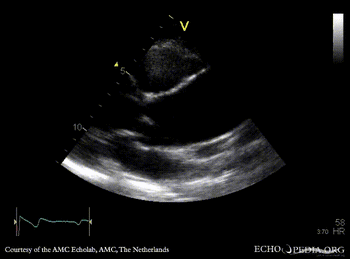

PLAX: dilated ascending aorta in patient with bicuspid aortic valve PSAX: bicuspid aortic valve